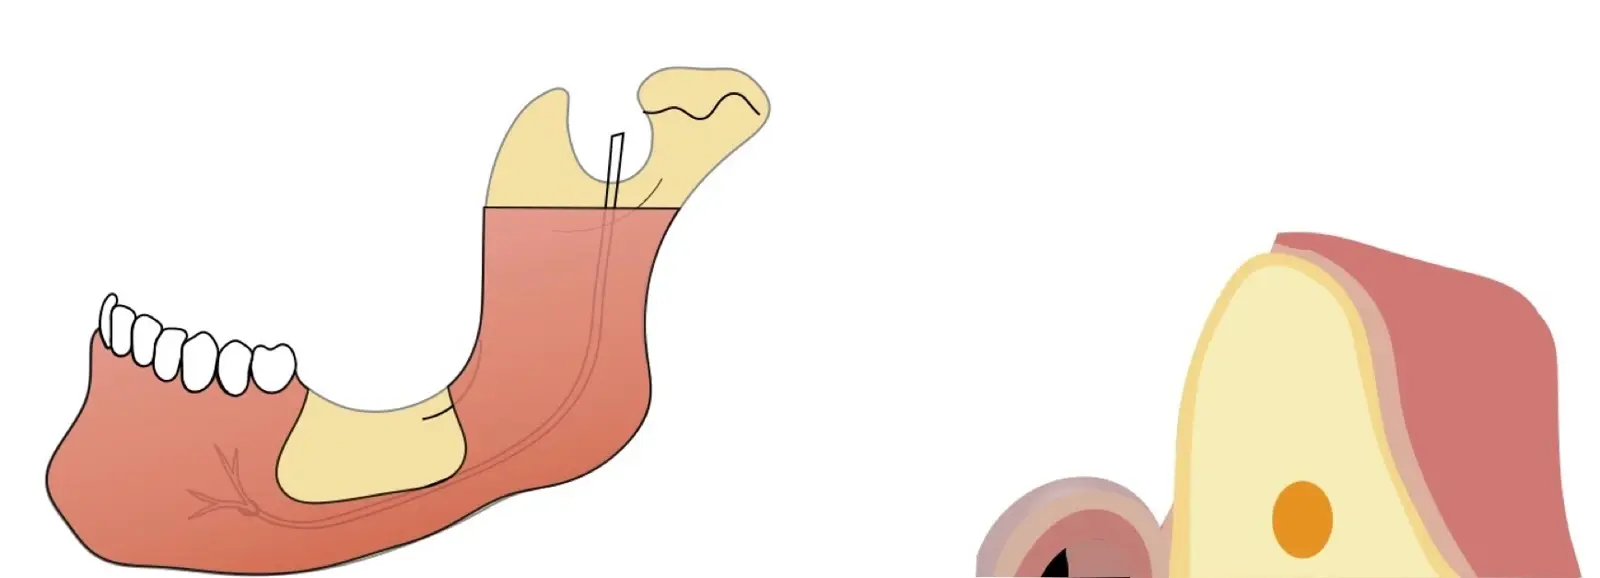

El hueso autógeno, considerado como el “gold stándard” para la regeneración ósea, no produce reacciones inmunológicas y contiene componentes osteogénicos, osteoinductores y osteoconductores.7,8 Suele obtenerse en bloques y las zonas dadoras intraorales de elección son la sínfisis mentoniana y la rama mandibular.9

La literatura menciona varias complicaciones relacionadas con la extracción de injertos óseos, la mayoría de ellas asociadas con el corte y la manipulación de zonas próximas a estructuras de riesgo; entre las más comunes, las lesiones nerviosas con consecuente adormecimiento, molestias postoperatorias (abertura bucal limitada, sangrado, hinchazón y dolor) y problemas estéticos (cambios en el contorno del área donadora o recesión de tejidos blandos).10 Aunque los injertos de rama pueden presentar menos molestias postoperatorias, tienen un acceso quirúrgico limitado debido a la apertura bucal y el peligro potencial de lesionar el paquete vásculo-nervioso cercano.11

La osteotomía con insertos de piezoeléctrico nos permite un corte más definido con menor pérdida de hueso residual, ya que los insertos son extremadamente finos.